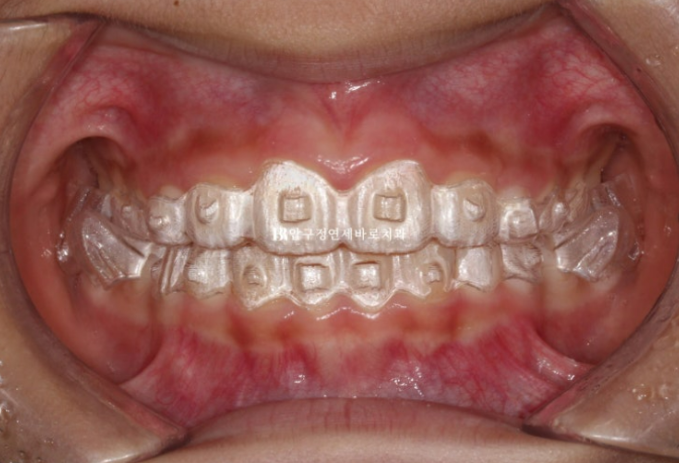

23.09

맞아진 위 아래 앞니 중심선과 개선된 과개교합

돌출된 앞니도 제자리로 들어갔습니다.